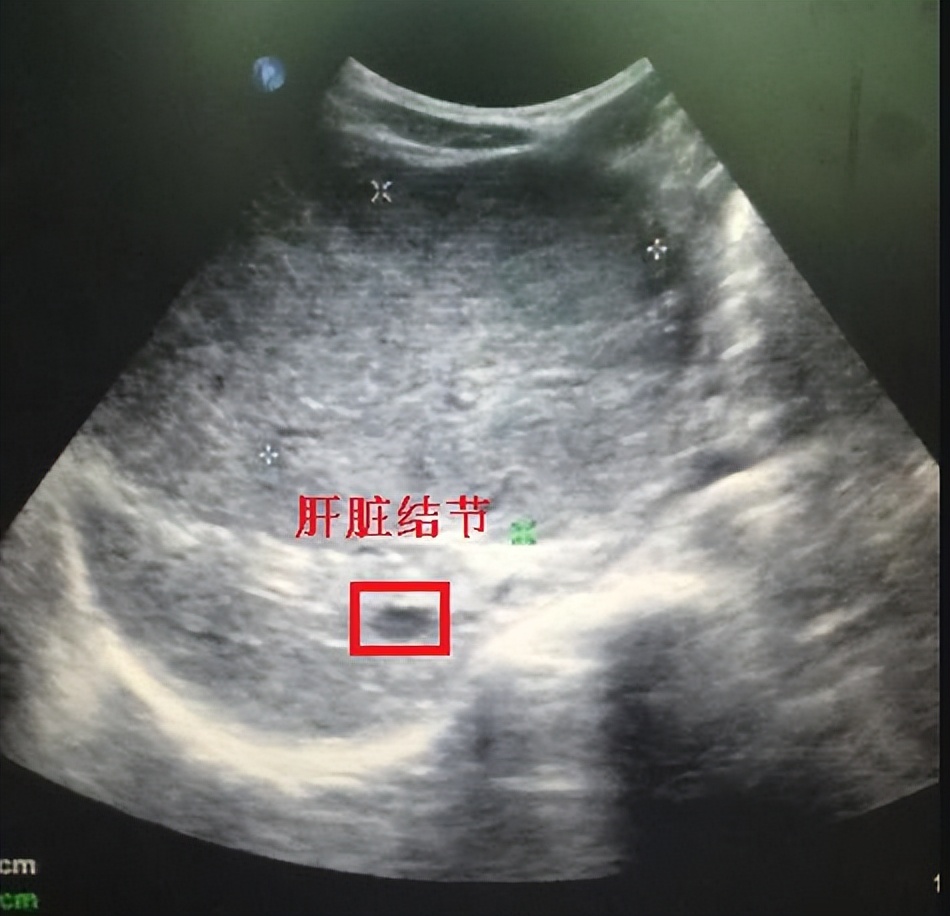

在中医看来,酒精是一种性质热盛的“发物” ,对人体的阴阳平衡有着潜在的影响。 据研究表明, 长期饮酒会增加肝部结节癌变的风险, 这是因为酒精会加重肝脏对酒精的代谢,增加血液中酒精含量水平,从而刺激肝脏组织细胞的异常生长。

此外,在生活中应该更加注重日常的饮食及注意保持身体的健康,避免吃过多辛辣刺激性的食物,保持良好的生活习惯,增强体质, 预防肝脏结节突发恶化癌变的发生。

总之,从中医角度来看,酒精的最佳摄入量为0,只要摄入就会对身体的阴阳平衡造成影响,增加肝脏结节恶化癌变的风险。 因此,在饮酒时需要适量控制,结合个人身体状况进行选择,同时要注重日常的饮食及生活习惯,以保持身体的健康。